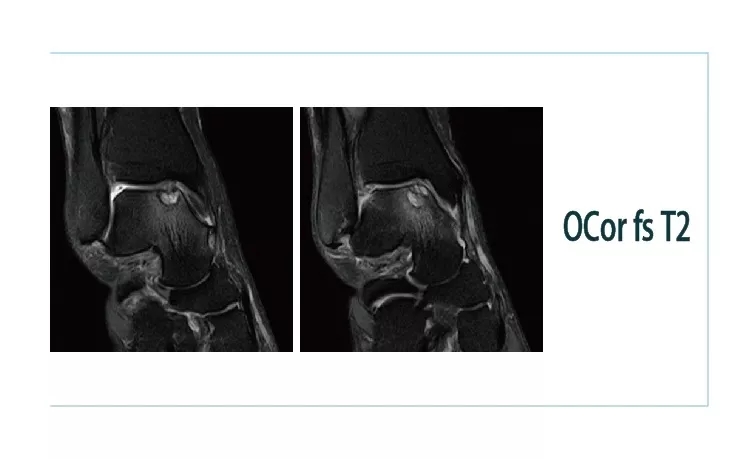

【朗润影像档案】20181102磁共振影像病例结果讨论